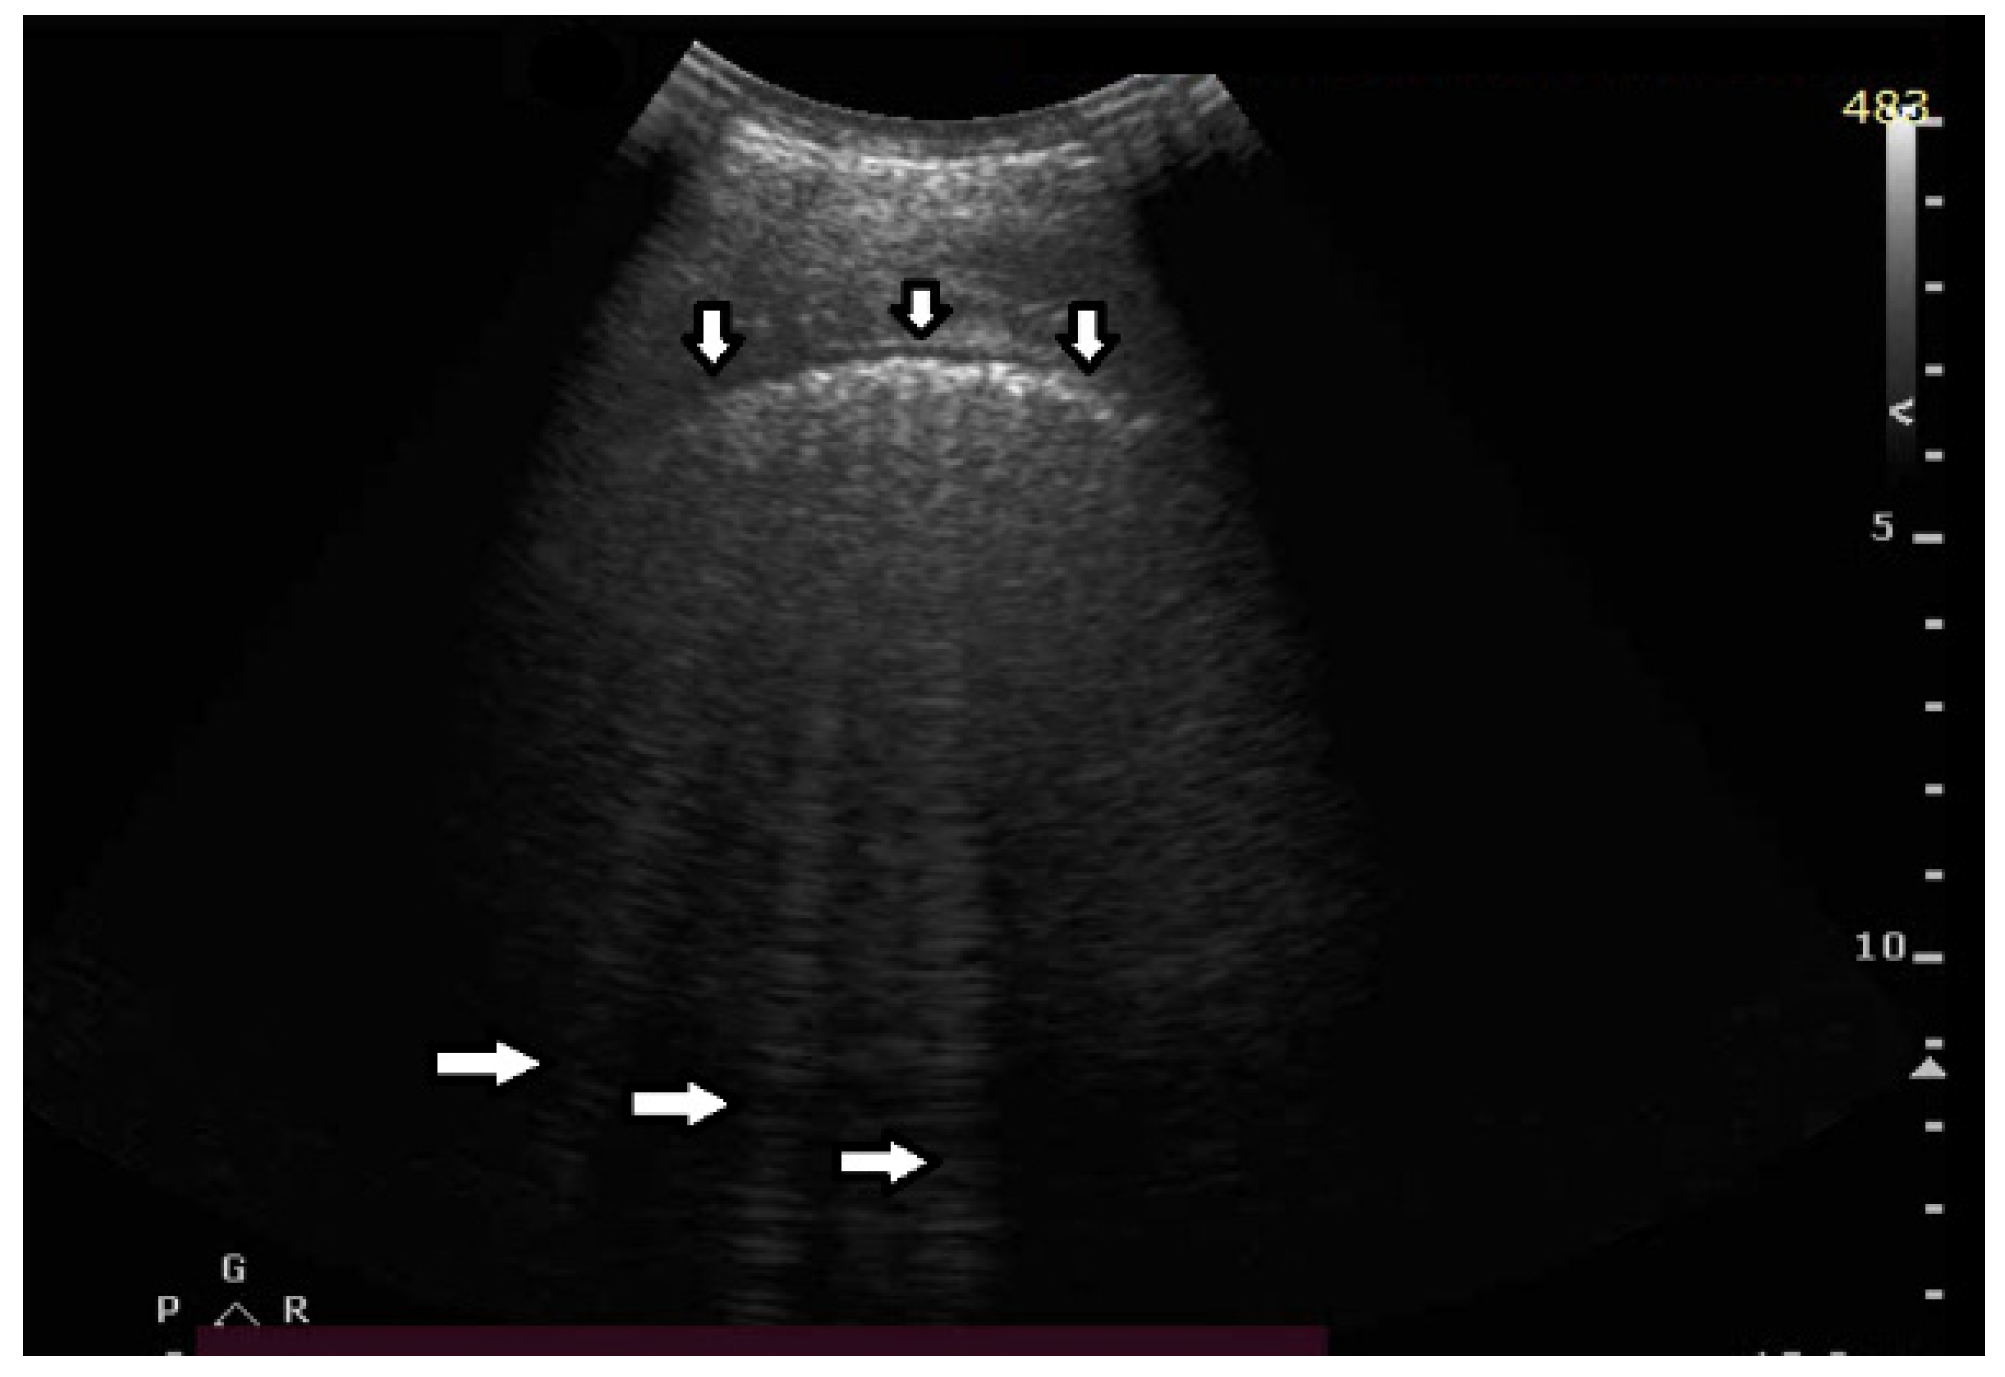

In healthy individuals, an ultrasound examination of the lungs visualizes only the lung surface, termed the pleural line (see Figure 2a). A-line artifacts are visible below the pleural line. These form horizontal lines that appear at regular intervals, equaling the distance between the body surface and the pleural line (see Figure 2b). Under anatomical conditions, it is not possible to visualize lung parenchyma and the interstitium. Only when subpleural areas of the lungs lose their aeration due to lesions can vertical artifacts and/or subpleural consolidations be observed [7]. Why is this so?

Once an US pulse reaches the pleura plane through the chest wall, it is partially reflected toward the probe and partially transmitted to the channels provided by a specific distribution of the aerated spaces, which characterizes the outer lung surface. In a healthy lung, the size of the interalveolar septa is, and reasonably so, supposed to be comparable to a capillary lumen (less than 10 microns), and an US pulse “sees” this aerated space distribution as a compact air wall. In this case, the acoustic energy is essentially reflected back to the probe. The lung surface is highlighted with a thick white line (the so-called pleural line), and A-line artifacts are visible below the pleural line thanks to the multiple reflections of the acoustic wave between the lung surface and the probe. Replicas of the thoracic wall structures are also often well visible between every pair of A lines thanks to the replica and mirror effects as a consequence of the strong reflection of the lung surface. It is worth noting, however, that the affirmation “The A line artifacts form horizontal lines that appear at regular intervals equaling the distance between the body surface and the pleural line” is not entirely correct. Such an affirmation is correct only if the pleural plane is exactly parallel to the head of the probe [8].

On the other hand, in the presence of thickened interstitial spaces, the pulse energy can be partially trapped by the latter. This can subsequently be reradiated toward the probe after multiple reflections between the separated aerated spaces, giving rise to vertical artifacts, which arise from the pleura line. The imaging parameters play a fundamental role in the formation of the artifacts, and the visibility of a vertical artifact (that is, its brightness, lateral dimension, and length) depends on multiple non-orthogonal factors including the gain, the time gain compensation (TGC), and all the parameters that can be easily set by the operator from the scanner keyboard. The clinical information that can be obtained from lung US images is essentially artifactual information except in the case of consolidation when anatomical information is obtained.

Figure 2. (a) Lung ultrasound, linear probe: white stars (*) muscles of the chest wall; down arrow () well-defined pleural line (perpendicular ultrasound beam); left arrow () blurred pleural line secondary to the tangential incidence of the ultrasound beam; up arrow () subcutaneous tissue; right arrow () A line, horizontal artifact. (b) Lung ultrasound, convex probe: down arrow—pleural line, smooth, echoic and regular; left arrow—A-line artifact.